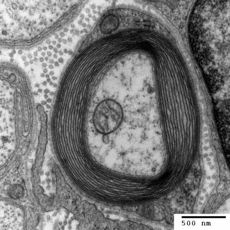

Myelin je lipoprotein, tvořící díky několikerému natočení lipidové dvojvrstvy buněčných membrán příslušných buněk kolem axonů (neuritů) neuronů obaly známé jako myelinové pochvy. Je jednou ze základních složek bílé hmoty mozku a míchy a je příčinou její bílé barvy. Jeho existence a správná distribuce (myelinizace) je nezbytnou podmínkou řádného fungování centrální (CNS) i periferní (PNS) nervové soustavy.

V prvním (iniciálním) úseku je axon obnažen, až v dalším jej u nemylienizovaných vláken obklopí Schwannova pochva, u myelinizovaných pak i myelinová pochva. Základem tukové složky jsou cerebrosid, sfingomyelin a cholesterol. Neurony CNS vytvářejí pochvu pomocí oligodendrocytů, kdy jeden oligodendrocyt slouží až pro 40 centrálně vedoucích axonů[1], postgangliová vlákna autonomního nerstva jsou vybavena pouze pochvou Schwannovou. V PNS ji tvoří Schwannovy buňky a pochva je zde přerušována Ranvierovými zářezy, ve kterých jsou koncentrovány mitochondrie. V těchto odhalených místech může docházet k větvení axonu.

Myelinová pochva funguje jako izolant a čím je vlákno silnější, tím jsou myelinové segmenty mezi zářezy delší, což urychluje vedení vzruchu. Rozdíly v rychlosti vedení jsou mezi nemyelinizovanými a silnými myelinizovanými vlákny až o dva řády ve prospěch druhých jmenovaných.[2] Byl objeven v roce 1854 německým patologem a biologem Rudolfem Virchowem.